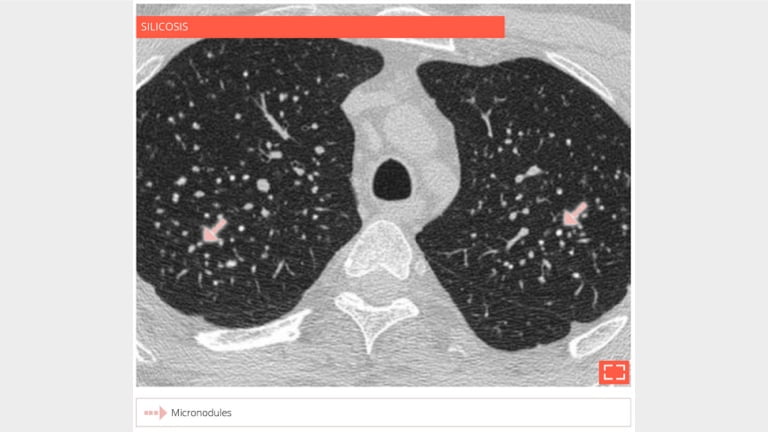

1. Micronodulation, perilymphatic distribution

Micronodulation, perilymphatic distribution

• Coal workers’ pneumoconiosis.

• Extensive micronodulation with a perilymphatic distribution. Micronodules have an apical and posterior predominance.